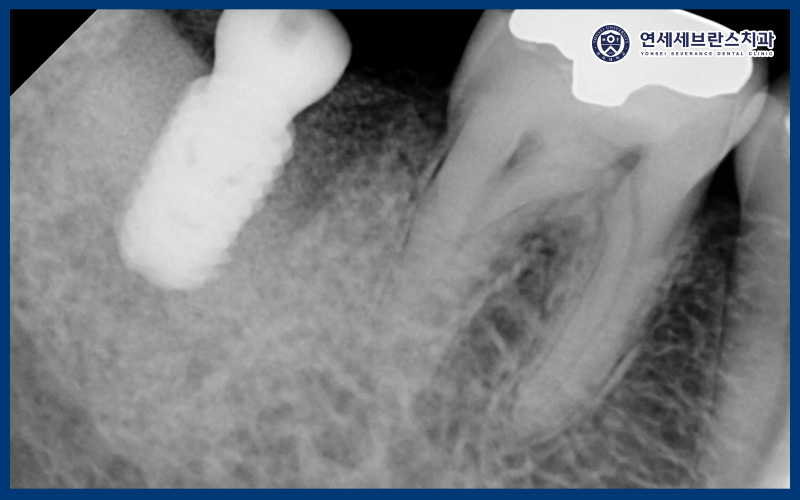

24.08.06

먼저 재신경치료를 위해

기존 크라운을 제거 한 후

내부를 확인해보았습니다.

예상대로 내부 오염이 심하며

전부 제거하니 잔존치질이

얼마 없는 상태로

환자분께 말씀드린 후 발치와

임플란트를 진행하기로 결정하였습니다.

24.08.14

먼저 발치를 진행하였으며

치조골 소실로 인해 뼈가 부족하여

뼈이식을 동반하여 곡반정동임플란트

식립을 하였습니다.